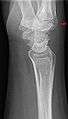

| Carpal boss in plain X-Ray. |

The joint between the index metacarpal and the capitate is a fibrous non-mobile joint. Some people have a gene that leads to this growth. It looks like arthritis (bone spurs on each side of the joint) on X-ray. It looks like a ganglion on the hand, but more towards the fingertips.